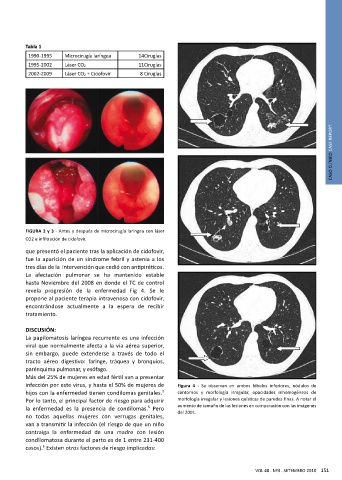

FIGURA 2 y 3 - Antes y después de microcirugía laríngea con láser

CO2 e infiltración de cidofovir.

La afectación pulmonar se ha mantenido estable

hasta Noviembre del 2008 en donde el TC de control

revela progresión de la enfermedad Fig 4. Se le

infección por este virus, y hasta el 50% de mujeres de Figura 4 - Se observan en ambos lóbulos inferiores, nódulos de

hijos con la enfermedad tienen condilomas genitales. contornos y morfología irregular, opacidades inhomogéneas de

Por lo tanto, el principal factor de riesgo para adquirir morfología irregular y lesiones quísticas de paredes finas. A notar el

la enfermedad es la presencia de condilomas. Pero aumento de tamaño de las lesiones en comparación con las imágenes

del 2001.